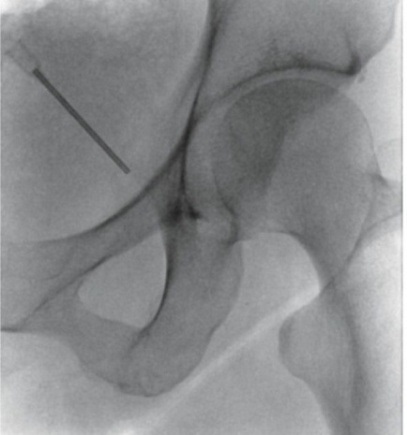

Πρόκειται για δυο τεχνικές που στοχεύουν στη διακοπή της μετάδοσης των σημάτων πόνου κατά μήκος των νευρικών οδών. Η πρώτη μέθοδος χρησιμοποιεί ραδιοσυχνότητες για να το πετύχει αυτό και η δεύτερη υγρό άζωτο που είναι ψυκτικός παράγοντας. Εφαρμόζονται σε ξύπνιο ασθενή με τοπική αναισθησία και κάτω από ακτινοσκοπική καθοδήγηση. Προσφέρουν σημαντική ανακούφιση για μήνες και επαναλαμβάνονται ως πράξεις εάν χρειασθεί μετά το πέρας της διάρκειας δράσης.

Ο κίνδυνος επιπλοκών είναι χαμηλός. Στις επιπλοκές ανήκουν η λοίμωξη, η ανάπτυξη αιματώματος, η βλάβη νευρικών και γύρω δομών. Η κινητική βλάβη του νεύρου αποφεύγεται με τη χρήση παλμικής ραδιοσυχνότητας ή κρυοπηξίας.